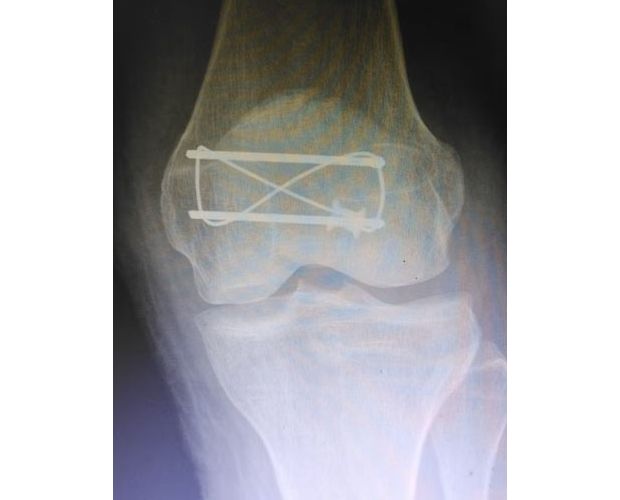

何店鎮(zhèn)中心衛(wèi)生院成功開展髕骨鋼板內(nèi)固定手術(shù)

——何店鎮(zhèn)中心衛(wèi)生院成功開展髕骨鋼板內(nèi)固定手術(shù)

隨州新聞網(wǎng)訊 (通訊員王靜、陳勇)為深入推進(jìn)緊密型醫(yī)共體建設(shè),切實(shí)讓轄區(qū)群眾在家門口就能享受到優(yōu)質(zhì)、便捷的醫(yī)療服務(wù),以醫(yī)療便民舉措為優(yōu)化營商環(huán)境注入健康活力,3月31日中午,何店鎮(zhèn)中心衛(wèi)生院(隨州市曾都區(qū)人民醫(yī)院何店分院)依托醫(yī)共體資源優(yōu)勢,特邀曾都區(qū)人民醫(yī)院脊柱創(chuàng)傷外科主任徐三軍到該院,成功為一名47歲髕骨骨折患者實(shí)施髕骨骨折切開復(fù)位內(nèi)固定手術(shù),用專業(yè)診療守護(hù)群眾健康,用務(wù)實(shí)行動踐行便民宗旨。

手術(shù)現(xiàn)場,徐三軍主任憑借多年積累的臨床經(jīng)驗(yàn)和嫻熟的手術(shù)技巧,精準(zhǔn)完成骨折復(fù)位、鋼板內(nèi)固定、傷口縫合等一系列關(guān)鍵操作,動作規(guī)范流暢、精準(zhǔn)高效,最大限度減少手術(shù)創(chuàng)傷。該院外科醫(yī)護(hù)團(tuán)隊(duì)全程密切配合、協(xié)同發(fā)力,嚴(yán)格按照手術(shù)規(guī)范操作,全程嚴(yán)密監(jiān)測患者心率、血壓等生命體征,及時應(yīng)對術(shù)中各類突發(fā)情況,全力保障手術(shù)安全。此次手術(shù)全程順利,術(shù)中出血量少,患者生命體征始終平穩(wěn),術(shù)后患者順利安返病房,為后續(xù)康復(fù)治療奠定了堅(jiān)實(shí)基礎(chǔ)。